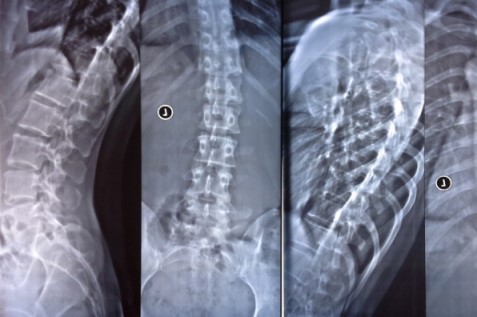

病院で側弯症と診断されても、特に軽度の場合は「経過観察(様子を見ましょう)」となることがほとんどです。数ヶ月から一年に一度、レントゲンを撮って進行を確認する。 しかし、これでは**「悪化していくのをただ待っている」**のと変わりません。

最近、当院に来られた高校生の方は、小学5年生で診断されてからずっと「様子見」でした。しかし、高校生になりカーブ(コブ角)が一気に進行。レントゲンを確認した時、骨の成長が止まる直前の時期でした。

丁寧なレントゲン画像分析(今の状態を正確に知る)